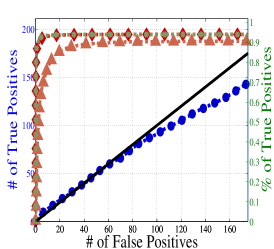

To understand the performance of this standard method, we present a small preview of our simulation study discussed later in Section 4. Briefly, we assume that each subject graph in group follows a small-world structure on nodes; in group , there are in addition 150 differential edges, meaning that and for all differential edges, . We generate data according to this model with time points and subjects in each group. Figure 1 illustrates the results of this standard approach as well as our new procedure, , which we will introduce later in Section 3. Part (a) gives ROC curves for the number of false positives verses true positives as each sequential test is rejected; parts (b) and (c) give the adjacency confusion matrix illustrating where the true and false positive as well as false negative edges are detected in the graph structure.

Our motivating simulation shows that the standard approach performs terribly in terms of both error control and statistical power. While the magnitude of the poor performance of this approach may seem astonishing, the poor performance should come as no surprise: The inferential procedure (e.g. test statistics) of the standard approach assume a one-level model that would be appropriate when the subject graphs are fixed and known or directly observed quantities. When these subject networks are unobserved, however, and must be estimated from finite data, these one-level test statistics are incorrect for our two-level problem. Specifically for two-level problems, the variance of parameters estimated by incorrectly assuming a one-level models is underestimated. For our problem, the extra source of variability arises from the graph selection procedure; we discuss challenges associated with this subsequently in Section 2.2. Incorrect variance estimates, however, are not the only problem with the standard approach: A more subtle problem arises from the fact that the proclivities of graph selection procedures for the Gaussian graphical model lead to biased estimates of the edge proportions, . As discussed in Section 2.3 and seen in Fig 1, graph selection false positives and false negatives do not occur at random throughout the network structure, leading to biased group level estimates.

Hence, the first term represents variability across subjects in group and the second term represents the variability associated with the selection procedure within subject , a quantity that we assume to be constant across subjects in each group . Consider now what happens if our true model follows this two-level Beta-Binomial model, but as with the standard approach, we use a one-level Binomial model and associated two-sample test statistic. The variance is thus underestimated and the test statistic is overoptimistic. Then, when inference is conducted for the population mean , using the incorrect Binomial model leads to inflated Type I error rates; this behavior has been well-documented (Weil, 1970; Liang and Hanfelt, 1994). Hence, failure to use the correct two-level model which accounts for the two levels of network variability partially explains the high error rates of the standard procedure observed in Figure 1.

In Figure 4 and Table 1, we present our main simulation results comparing to the two variations of our method and the standard approach for three network structures and Case I and II type differential edges. First for Figure 4, we report results in terms of operating characteristics averaged across 50 replicates with the number of true positives (y-axis) plotted against the number of false positives (x-axis) for each test statistic, rejected sequentially from largest to smallest in absolute magnitude. Overall, all of our methods and particularly yield substantial improvements over the standard approach in all scenarios.

Notice that both and =(RS,RP) share similar orderings of test statistics, and consequently similar ROC curves. Overall, methods that include random penalization yield major improvements in statistical power over those that do not. This indicates that the second popPSI challenge outlined in Section 2.3 is a significant contributor to the poor performance of the standard method. Recall our discussion of how graph selection errors at the subject stage occur non-randomly and hence bias our group-level estimates of . Our results empirically demonstrate that random penalization dramatically improves these biases, leading to less bias in our test statistics and hence improvements in both Type I and Type II error rates. Furthermore, in Case II scenarios where selection errors are moderate, the performance gap between any method containing over reduces compared to Case I scenarios where selection errors are more severe. Thus, the benefits of random penalization are greater when selection errors are more abundant. Confusion adjacency matrices illustrating the location of inferential errors for our methods shown in the supplemental materials also indicate that random penalization improves graph selection in cases where there are larger correlations between differential edges and common edges. Similar results hold for our high-dimensional study presented in the supplemental material.

Table 1, which accompanies Figure 4, gives the empirical true positive and false discovery rates (FDR) averaged over 50 simulation replicates when the Benjamini-Yekutieli (Benjamini and Yekutieli, 2001) procedure controlling the FDR at 10% is used to determine the number of tests to reject. First, notice that the observed false discovery proportion (FDP) of our procedure is not 10% on average, indicating that our method does not fully control the FDR. This occurs because we specifically simulate difficult and realistic fMRI scenarios with graph structures that severely violate irrepresentable-type conditions. In situations (not shown) where irrepresentable-type conditions are met that ensure graph selection consistency, our procedure as well as the standard method correctly control the FDR. As discussed in Section 2.3, in situations where graph selection errors occur with high probability, it is likely impossible to provably control the FDR, consistent with our empirical results. Yet even though does not fully control the FDR, our error rates are dramatically improved over the standard approach and other variations of our procedure.

Also in Table 1, observe that (RS,RP), which had similarly ordered test statistics to , has dramatically worse Type I error rates that do not come close to controlling the FDR. While (RS,RE) also does not control the FDR, the error rates are much improved over (RS,RP). These results demonstrate that using two-level models with the correct random effects test statistics are crucial to Type I error control. Recall from Section 2.2, that using the one-level Binomial model leads to an under-estimation of the variance term which in turn inflates test statistics and leads to an increase in false positives. Note also that the estimated FDP of is still a major improvement over that of (RS,RE). This occurs as the problem of graph selection errors induces both Type I and Type II errors. Hence, these results demonstrate the necessity of all three of our ingredients. Finally, observe that our error rates in Case II scenarios are better than those for Case I scenarios, again indicating that differential edges that are highly correlated with non-edges and common edges pose particular challenges for our popPSI problem. These results are also corroborated in our high-dimensional study presented in the supplemental materials.

Lastly, in Figure 5, we study the effect of letting the network structure vary across subjects by decreasing the differential group edge probability, . Our method continues to perform well for . However, when the differential edge probability drops further to , we see that both and the standard approach have greatly reduced statistical power, as one would expect. Despite this, continues to outperform the standard approach.